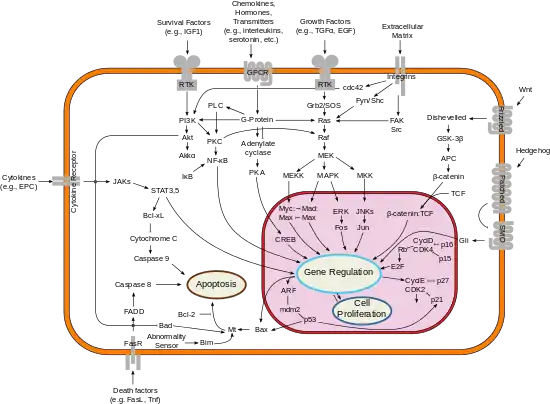

It is a well-established concept in the field of apoptosis that relative amounts of pro- and anti-survival Bcl-2 family of proteins determine whether the cell will undergo cell death; if more Bcl-xL is present, then pores are non-permeable to pro-apoptotic molecules and the cell survives. However, if Bax and Bak become activated, and Bcl-xL is sequestered away by gatekeeper BH3-only factors (e.g. Bim) causing a pore to form, cytochrome c is released leading to initiation of caspase cascade and apoptotic events.[2]

While the exact signaling pathway of Bcl-xL is still not known, it is believed that Bcl-xL differs highly from Bcl-2 in their mechanism of inducing apoptosis. Bcl-xL is about ten times more functional than Bcl-2 when induced by the chemotherapy drug, Doxorubicin[3] and can specifically bind to cytochrome C residues, preventing apoptosis.[4] It can also prevent the formation of Apaf-1 and Caspase 9 complex by acting directly upon Apaf-1 rather than Caspase 9, as shown in nematode homologs.[5]